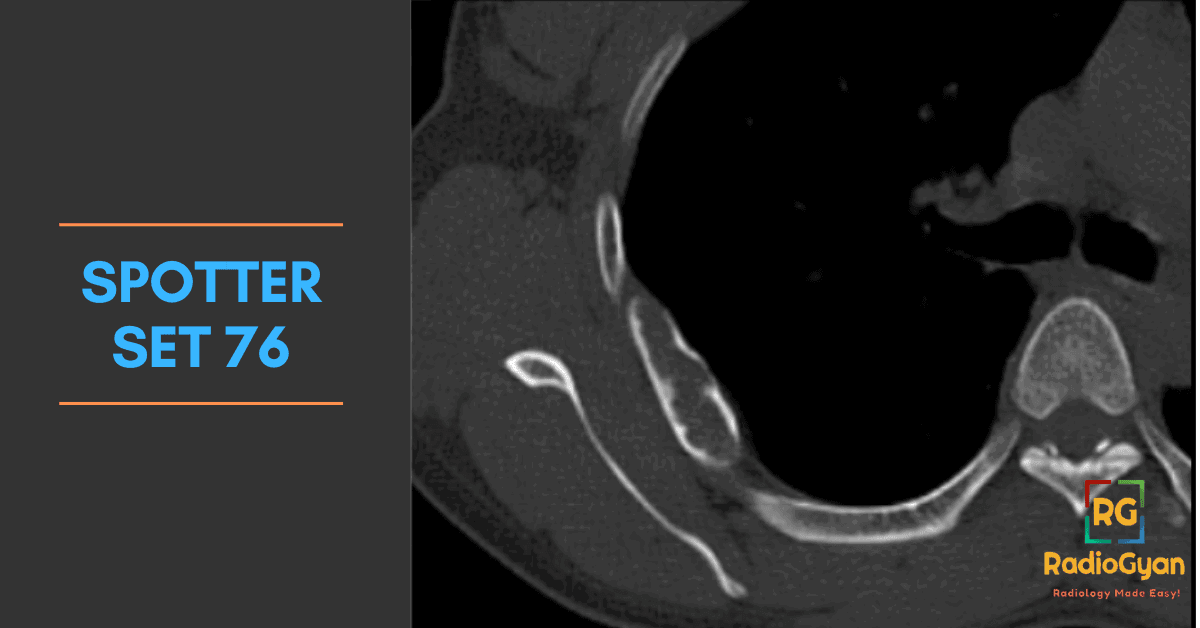

Explore high-yield radiology spotters with detailed explanations and case discussions to enhance your diagnostic skills at RadioGyan.com.